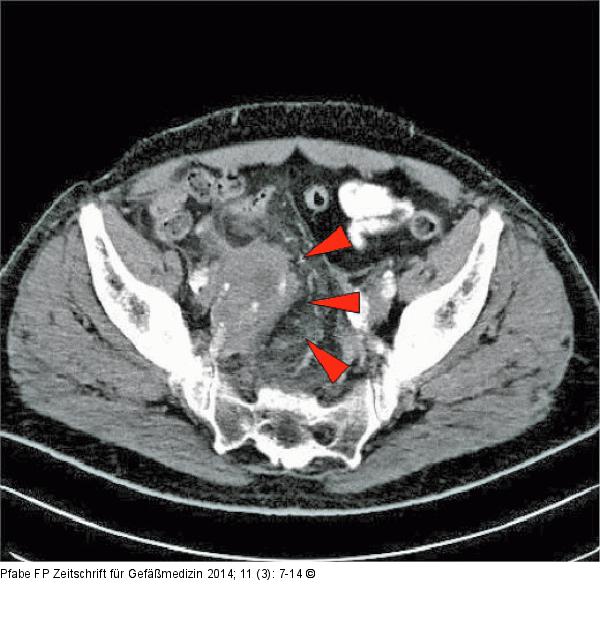

Abbildung 4: Iliakalaneurysma Retroperitoneales Hämatom (rote Pfeile) bei gedeckter Ruptur eines Aneurysmas der A. iliaca interna rechts. |

Retroperitoneales Hämatom (rote Pfeile) bei gedeckter Ruptur eines Aneurysmas der A. iliaca interna rechts. |